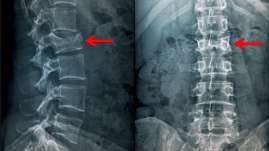

Produce Covid-19 fracturas vertebrales: Científicos italianos

Científicos italianos comprobaron la aparición frecuente de fracturas vertebrales en pacientes con la Covid-19, lo cual puede du...

Jue. 22 de oct., 2020. | 01:02 pm